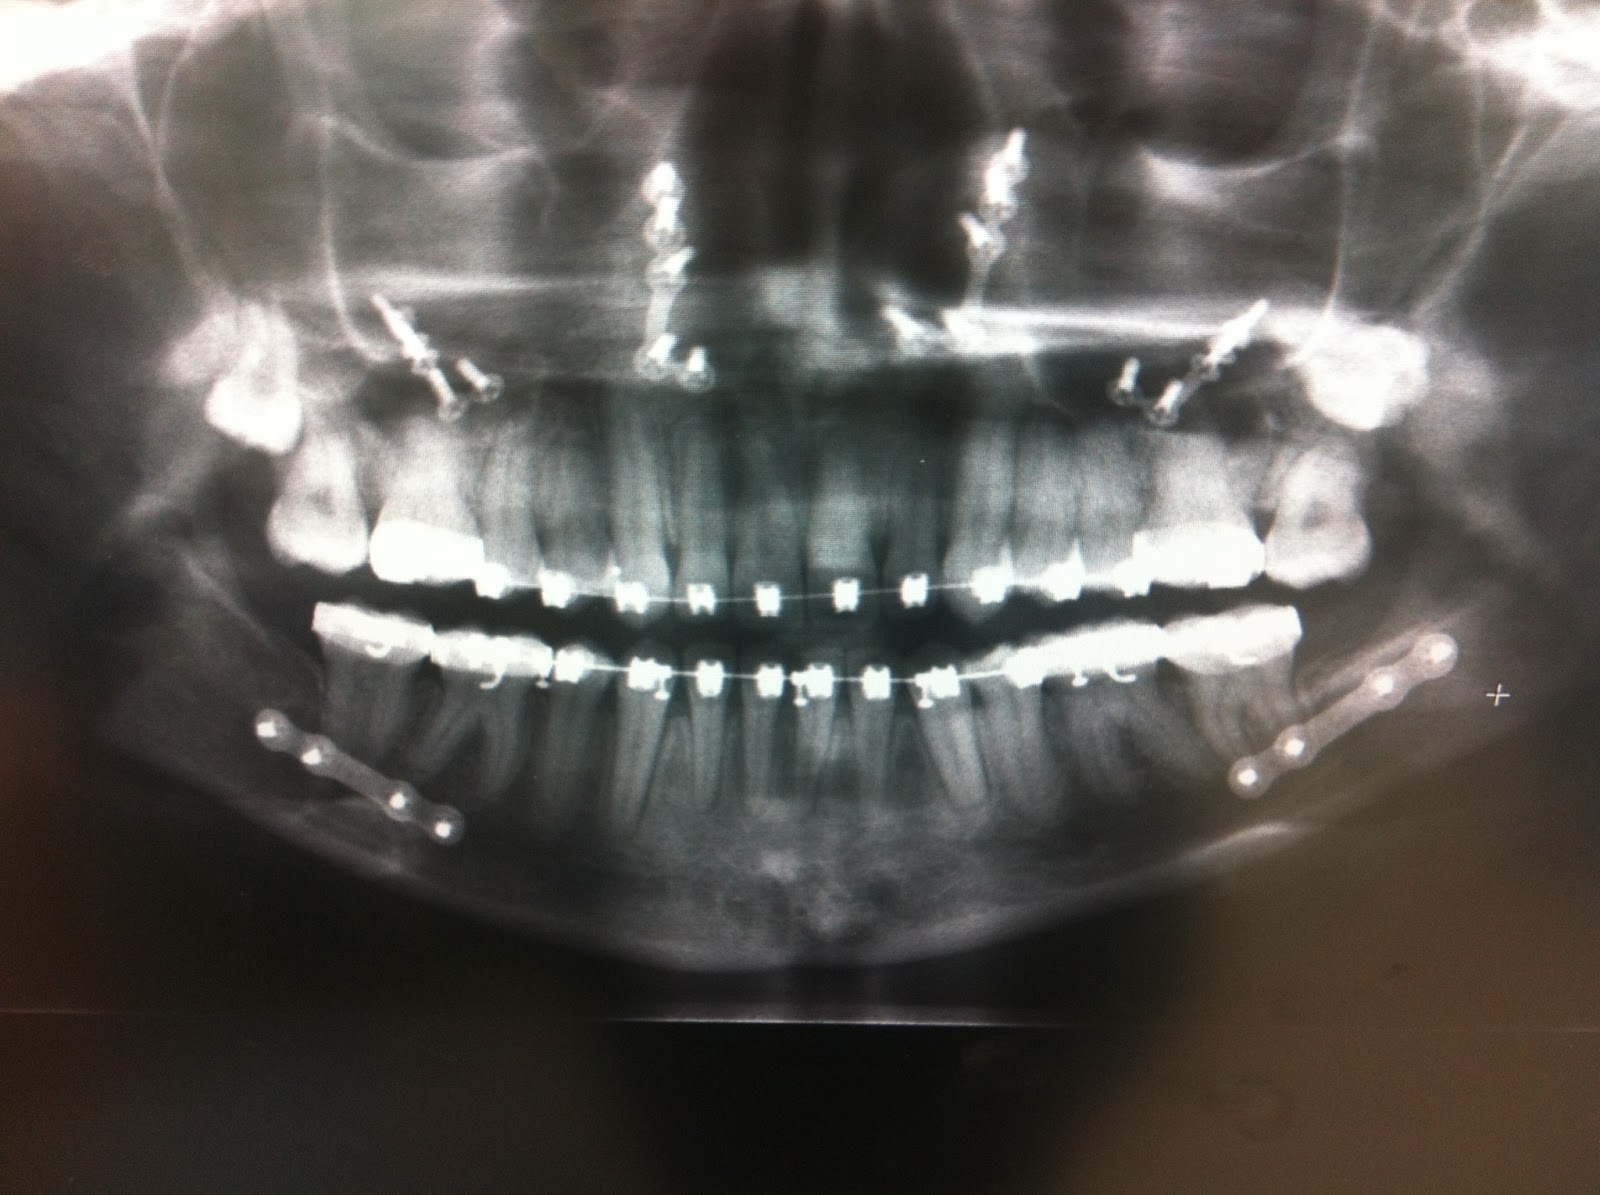

Panoramic Xray Of The Jaw After Fracture And Osteosynthesis With The Titanium Plate In Jaw Side Effects The titanium plates and screws in your upper. the toxicity of titanium implants revealed 734 results, including titanium corrosion and titanium. in this article, the authors will review the most common risk factors associated with metallic surgical implants. adverse effects reported in one study were two plate exposures in each group occurring between the third and. Here's. Titanium Plate In Jaw Side Effects.

Panoramic Xray of the jaw after fracture and osteosynthesis with the Titanium Plate In Jaw Side Effects side effects can include allergic reaction to the implant, bleeding, scarring, and more. in this article, the authors will review the most common risk factors associated with metallic surgical implants. Convenience most patients will be able to resume most normal daily activities after. adverse effects reported in one study were two plate exposures in each group occurring. Titanium Plate In Jaw Side Effects.